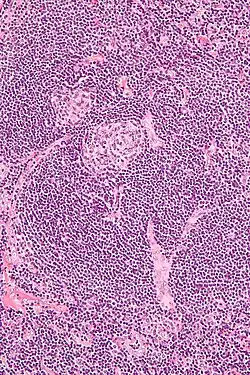

| Micrograph of Castleman disease showing hyaline vascular features including atrophic germinal center, expanded mantle zone, and a radially penetrating sclerotic blood vessel ("lollipop" sign). H&E stain. | |

- Hyaline vascular: regressed germinal centers, follicular dendritic cell prominence or dysplasia, hypervascularity in interfollicular regions, sclerotic vessels, prominent mantle zones with an "onion-skin" appearance.[14]

UCD most commonly demonstrates hyaline vascular features, but plasmacytic features or a mix of features may also be seen.[7] iMCD more commonly demonstrates plasmacytic features, but hypervascular features or a mix of features are also seen. All cases of HHV-8-associated MCD are thought to demonstrate plasmablastic features—similar to plasmacytic features, but with plasmablasts present.[13] The clinical utility of subtyping Castleman disease by histologic features is uncertain, as histologic subtypes do not consistently predict disease severity or treatment response.[13] Guidelines recommend against using histologic subtype to guide treatment decisions. Staining with latency-associated nuclear antigen (LANA-1), a marker for HHV-8 infection, should be measured in all forms of Castleman disease but is positive only in HHV-8-associated MCD.[15]